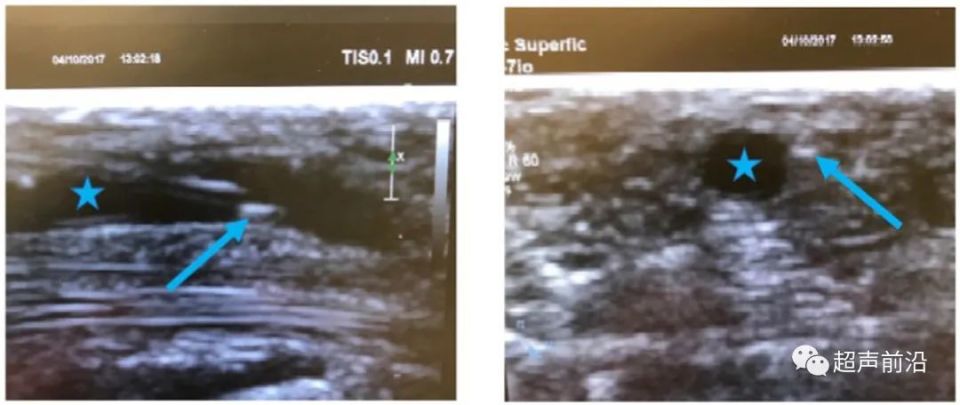

超声波束(三维)的形状和厚度由阵元尺寸和声透镜的组合决定,因此是固定的。声束的初始厚度等于压电元件高度,之后变窄,直到焦点深度处最小,然后再次发散。在超声成像时,放置在血管外侧的针头可能会被错误地显示为位于血管内,即所谓的切片厚度伪影(图 2)。图 2 左图:显示血管内放置针尖;图 2 右图:同一穿刺图像显示在血管内腔(蓝色星)外放置针尖(蓝色箭头)。

图2:切片厚度伪影